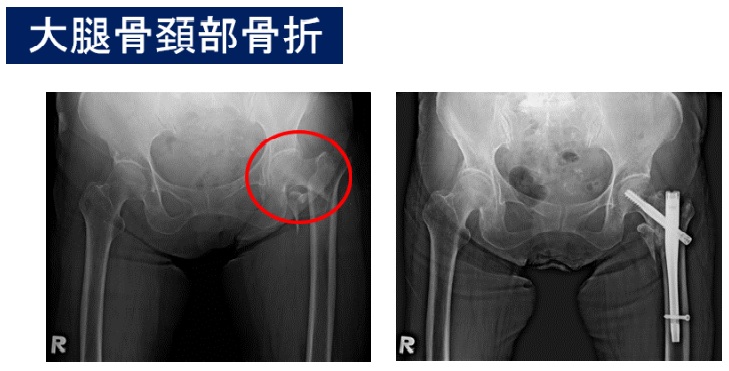

頚部骨折とop後

左が手術前の左大腿骨頚部骨折の写真です。右は骨折部位を器械で固定した写真です。手術を行わなければ、歩行能力を喪失することになるため、ほとんどの場合、手術の適応となります!